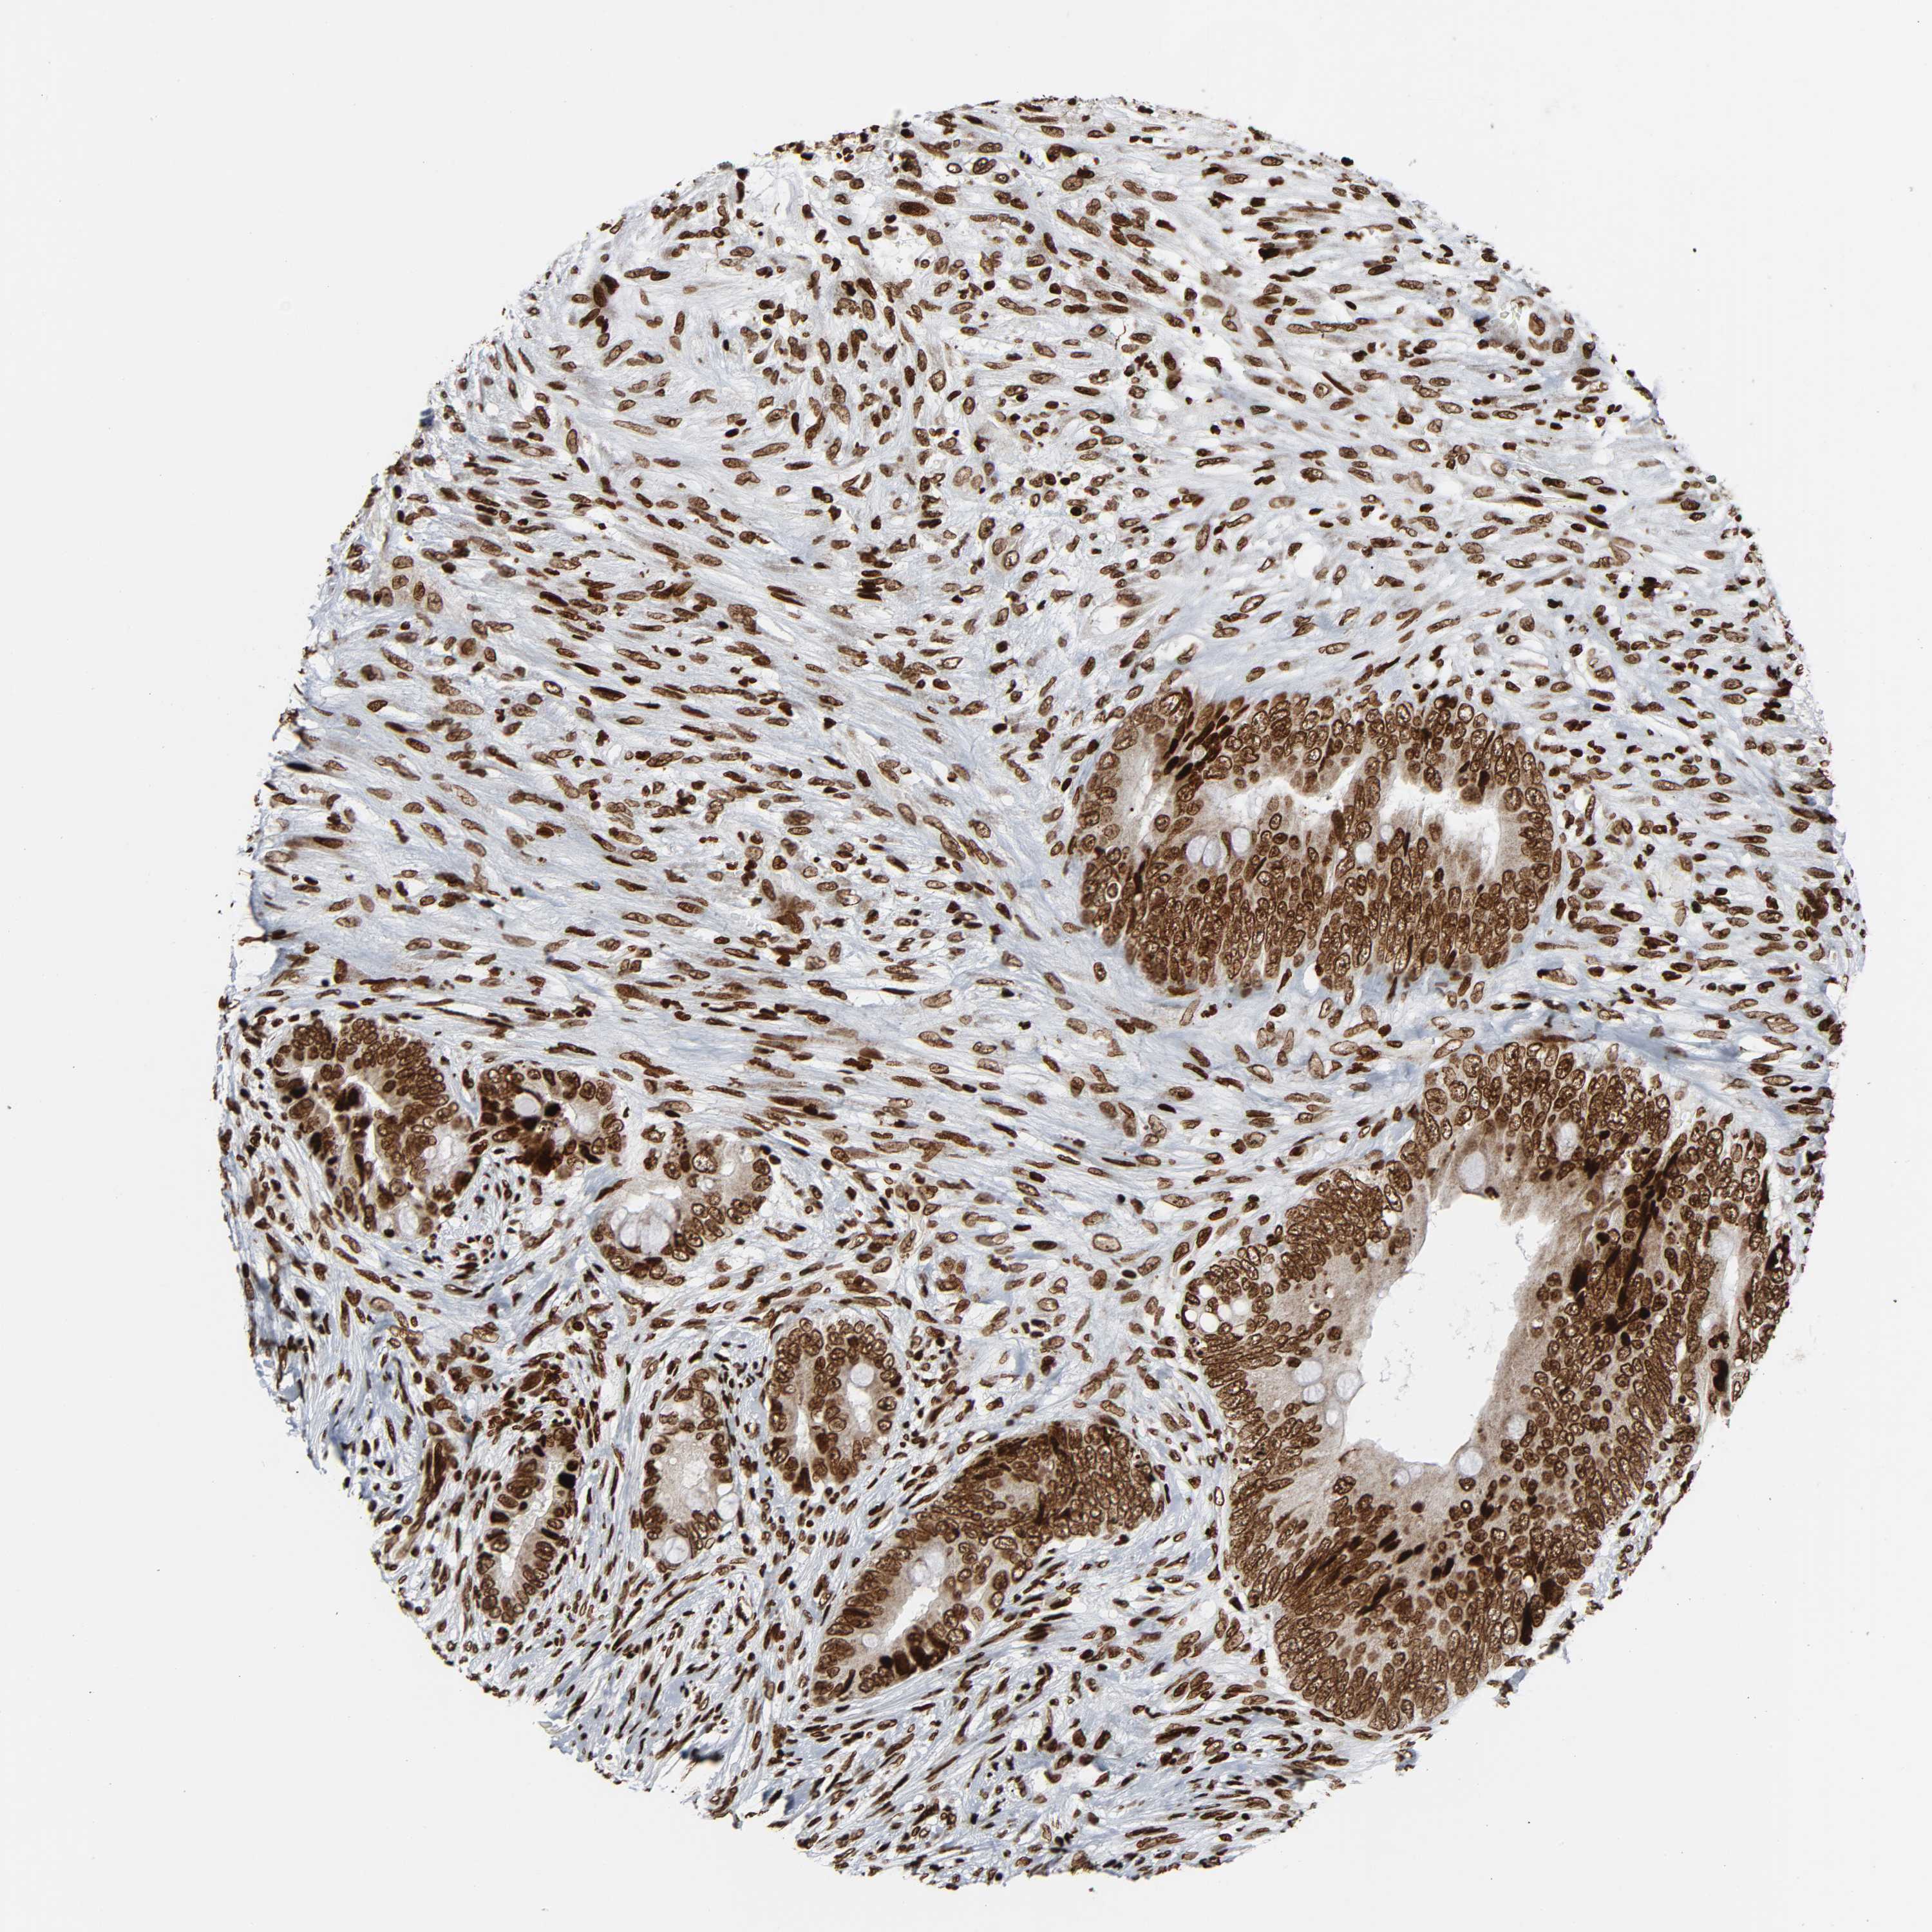

CANCER COLORECTAL CANCER Show tissue menu

Colorectal cancer

Human cancer

Colon adenocarcinoma